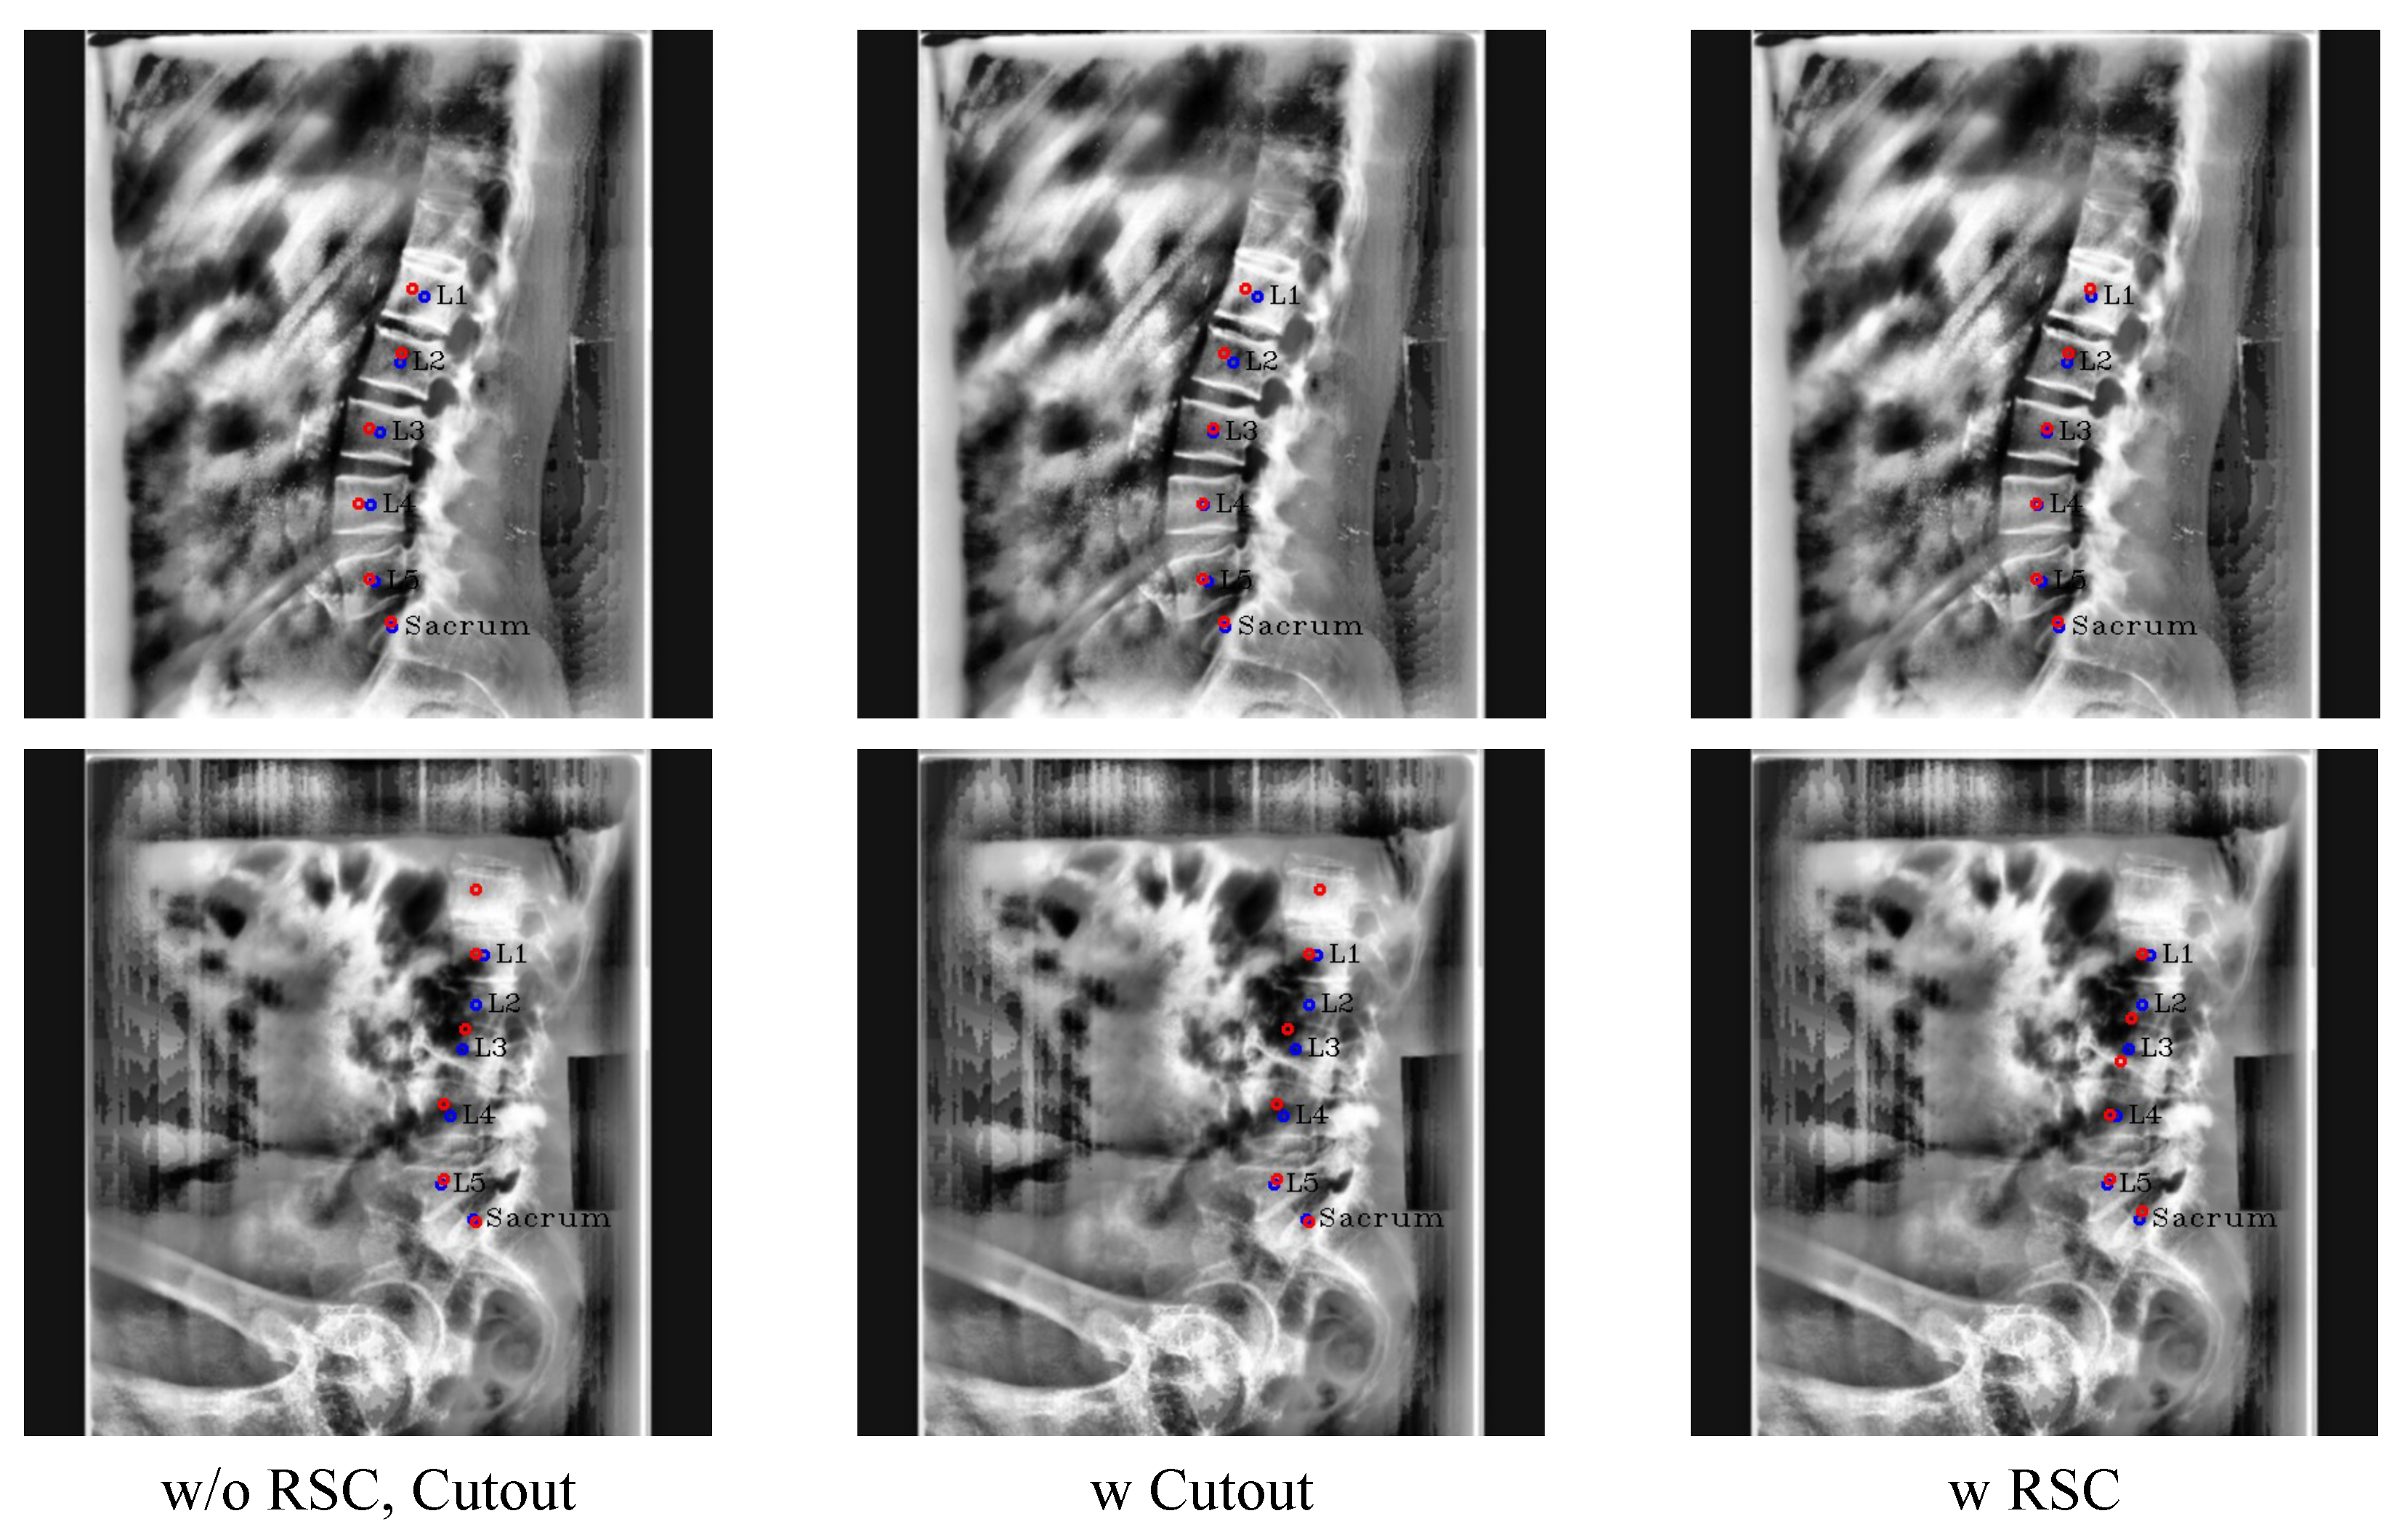

Figure 12. Results of ablation study with the conventional cutout and RSC. The red circles denote the predicated centers of L1, L2, L3, L4, L5, and the sacrum in order from the top, and blue circles and labels denote the ground truth of the centers.

We quantitatively and qualitatively compared the performance of the conventional cutout [8] and RSC. When using the conventional cutout, we set the region of the cutout similar to that of the RSC region.

Table 4 shows the benefit of RSC. In Table 4, we can see that training Pose-Net with RSC and the conventional cutout showed good performance in the distance error. However, unlike RSC, when using the conventional cutout only, the outlier ratio was higher than without the cutout. Since occlusion is a common feature of X-ray images, both RSC and the conventional cutout were effective in reducing the distance errors. However, our RSC on the lumbar vertebrae (L1–L4) was more effective in drastically decreasing the distance error and outlier ratio.

We also compared RSC and the conventional cutout qualitatively in Figure 12. As illustrated in the first row of Figure 12, the centers of L3 and L4 were more precisely localized when either RSC or the conventional cutout was employed compared to the results without cutout augmentation. Where the center area was occluded like L1, the predicted center of L1 was skewed to the left when using the conventional cutout technique. In contrast, in the case of RSC, the center of L1 was accurately predicted. Moreover, only RSC can drive Pose-Net to accurately detect sequential L1 to L3, even when it is difficult to visually distinguish the boundary between L2 and L3, as shown in the second row of Figure 12. Therefore, it is evident that RSC is superior to the conventional cutout technique in the lumbar X-ray image and can make Pose-Net more robust in circumstances where the vertebrae are not clearly visible by cutting only the lumbar vertebrae.